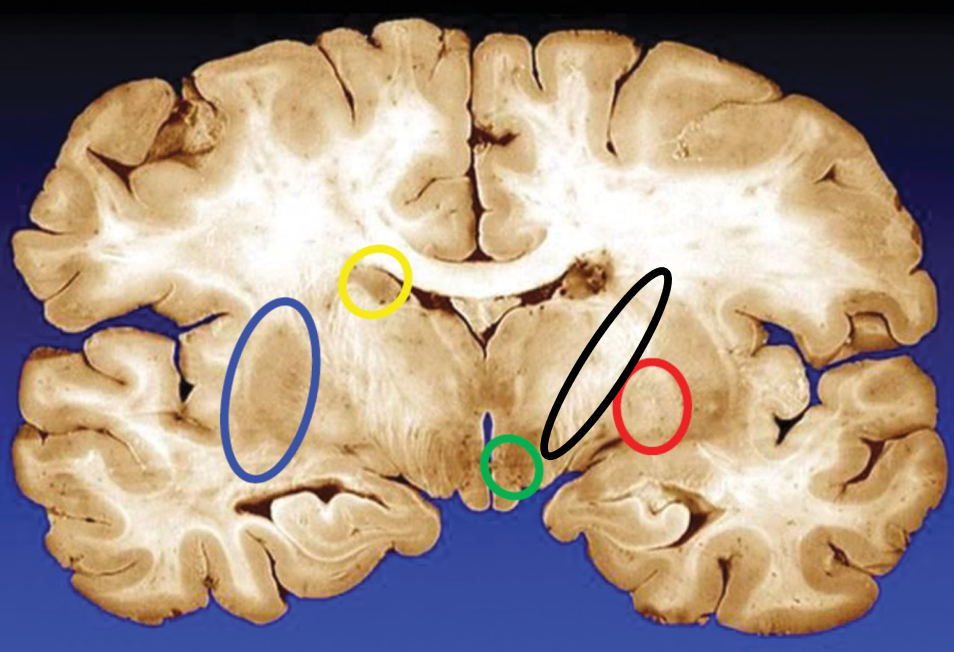

blue

putamen

yellow

caudate

green

subthalamic nuclei

black

internal capsule

red

globus pallidus

name the condition

Huntington’s (reduced caudate)